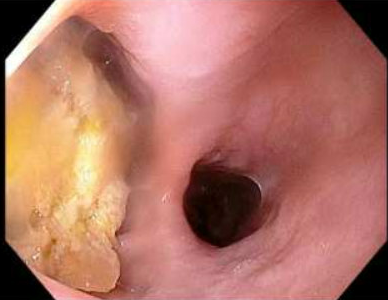

Zenker peroral endoscopic myotomy was performed under general anesthesia. EGD was performed and all the food contents from the pouch were removed (Fig. 2). A guidewire was passed through the esophageal lumen for identification during procedure. Saline with methylene blue was injected along the cricopharyngeal ridge and a mucosal incision was made along the ridge using a Triangular tip knife (TTJ Olympus, America) using ENDOCUTQ current (ERBE). Submucosal dissection was done to form a tunnel using spray coagulation and the esophageal mucosa and diverticular mucosa were separated from the cricopharyngeus muscle. Then a complete cricopharyngeal myotomy was performed using the same Triangular tip knife until the buccopharyngeal fascia was reached (Fig. 4 & 5). After complete hemostasis, the mucosal incision was closed using through-the-scope clips (Microtek). A total of five clips were used for the closure (Fig. 6).

Figure 3: Esophagogastroduodenoscopy of Zenker and esophagus with guidewire placed in the stomach for orientation during the procedure

Figure 3